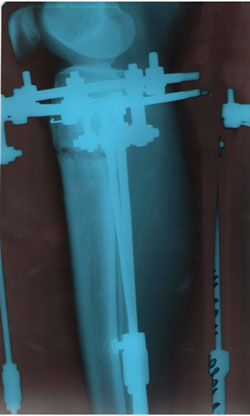

Дата операции 08.01.2014г.

Дата снятия аппаратов 15.04.2014г.

Срок лечения 98 дней.